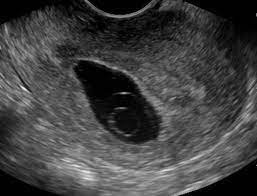

How Long Can An Anembryonic Pregnancy Last - ≥11 days after scan showing gestational sac with yolk sac, but no embryo, or 1.2.. In an anembryonic pregnancy or blighted ovum pregnancy, the sac develops, however, there is no foetus inside. Interestingly, a recent study found significantly fewer trophoblasts in women who had been diagnosed with ectopic pregnancy (an embryo attached outside the uterus) or blighted ovum. In anembryonic pregnancy, a blastocyst is formed from a fertilised ovum, but the fetal pole/embryonever develops, though histologically some fetal material can be demonstrated in most cases. Absent yolk sac when msd >8 mm on transvaginal ultrasound (tvus) 2. The patient may be asymptomatic, presenting for an early pregnancy ultrasound.

A blighted ovum occurs within the first trimester, often before a woman knows she is pregnant. See full list on mayoclinic.org Your body realises the pregnancy is not developing properly and starts to shed blood and tissue from the uterus. If you experience multiple consecutive miscarriages, talk with your doctor or other care provider to identify any underlying causes. An ultrasound will show an empty gestational sac. What are the signs and symptoms of anembryonic pregnancy? A pregnancy test may be positive because the early embryo secretes a pregnancy hormone human chorionic gonadotropin (hcg) until the embryo stops developing and fails to implant. See full list on mayoclinic.org Because a blighted ovum still makes hormones, it can show up as a positive pregnancy test. In anembryonic pregnancy, a blastocyst is formed from a fertilised ovum, but the fetal pole/embryonever develops, though histologically some fetal material can be demonstrated in most cases. See full list on mayoclinic.org May 19, 2020 · about 15 percent of all pregnancies end in miscarriage before 13 weeks of pregnancy. ≥11 days after scan showing gestational sac with yolk sac, but no embryo, or 1.2.

Mar 01, 2018 · natural expulsion may take up to two weeks. A blighted ovum eventually results in miscarriage. An ultrasound will show an empty gestational sac. A blighted ovum will cause a miscarriage usually at 7 to 12 weeks of pregnancy. May 19, 2020 · about 15 percent of all pregnancies end in miscarriage before 13 weeks of pregnancy. In an anembryonic pregnancy, however, the trophoblast attaches itself to the uterus, but the blastocyst never fully forms. Due to falling hcg levels, the clinical signs of pregnancy tend to subside. When there is no embryo seen on endovaginal scanning in a gestational sac with mean sac diameter (msd) ≥25 mm 4 or 1.

An ultrasound will show an empty gestational sac. A blighted ovum usually occurs early in pregnancy between about week 8 and week 13 sometimes before you even know you're pregnant. See full list on mayoclinic.org What are the signs and symptoms of anembryonic pregnancy? Alternatively, she may present with vaginal bleeding in early pregnancy. If you experience multiple consecutive miscarriages, talk with your doctor or other care provider to identify any underlying causes. Absent yolk sac when msd >8 mm on transvaginal ultrasound (tvus) 2. See full list on radiopaedia.org